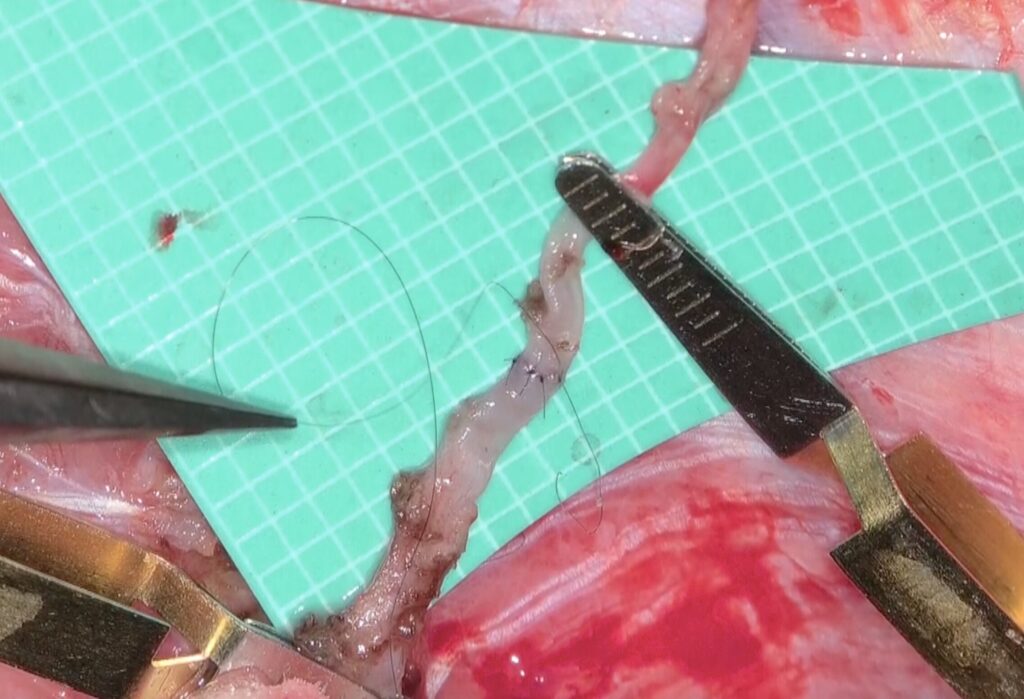

51歳女性の脳梗塞と脳室内出血を続けて起こした左片側もやもや病の患者さんをバイパス手術しました。STAがgaleaから外に出てGaleaの外に枝を出していたため皮弁翻展時にSTA頭頂枝が切れてしまい、端端吻合をしてからバイパスに用いました。2本とも無事開通しました。脳血流が著明に低下していたので術後の過灌流が心配で厳重な術後血圧管理を行いましたが、幸い順調な回復を見せています。

51歳女性の脳梗塞と脳室内出血を続けて起こした左片側もやもや病の患者さんをバイパス手術しました。STAがgaleaから外に出てGaleaの外に枝を出していたため皮弁翻展時にSTA頭頂枝が切れてしまい、端端吻合をしてからバイパスに用いました。2本とも無事開通しました。脳血流が著明に低下していたので術後の過灌流が心配で厳重な術後血圧管理を行いましたが、幸い順調な回復を見せています。